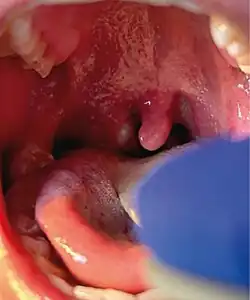

Mpox is a viral infection that manifests a week or two after exposure with fever and other non-specific symptoms, and then produces a rash with lesions that usually last for 2–4 weeks before drying up, crusting and falling off.[10] While mpox can cause large numbers of lesions, in this outbreak some patients experience only a single lesion in the mouth or on the genitals, making it more difficult to differentiate from other infections.[20] In previous outbreaks, 1–3 per cent of people with known infections had died (without treatment). In the 2022–2023 outbreak the rate of death was less than 0.2 percent. Cases in children and immunocompromised people are more likely to be severe.[21]

In addition to more common symptoms, such as fever, headache, swollen lymph nodes, and rashes or lesions, some patients have also experienced proctitis, an inflammation of the rectum lining. CDC has also warned clinicians to not rule out mpox in patients with sexually transmitted infections since there have been reports of co-infections with syphilis, gonorrhea, chlamydia, and herpes.[98]